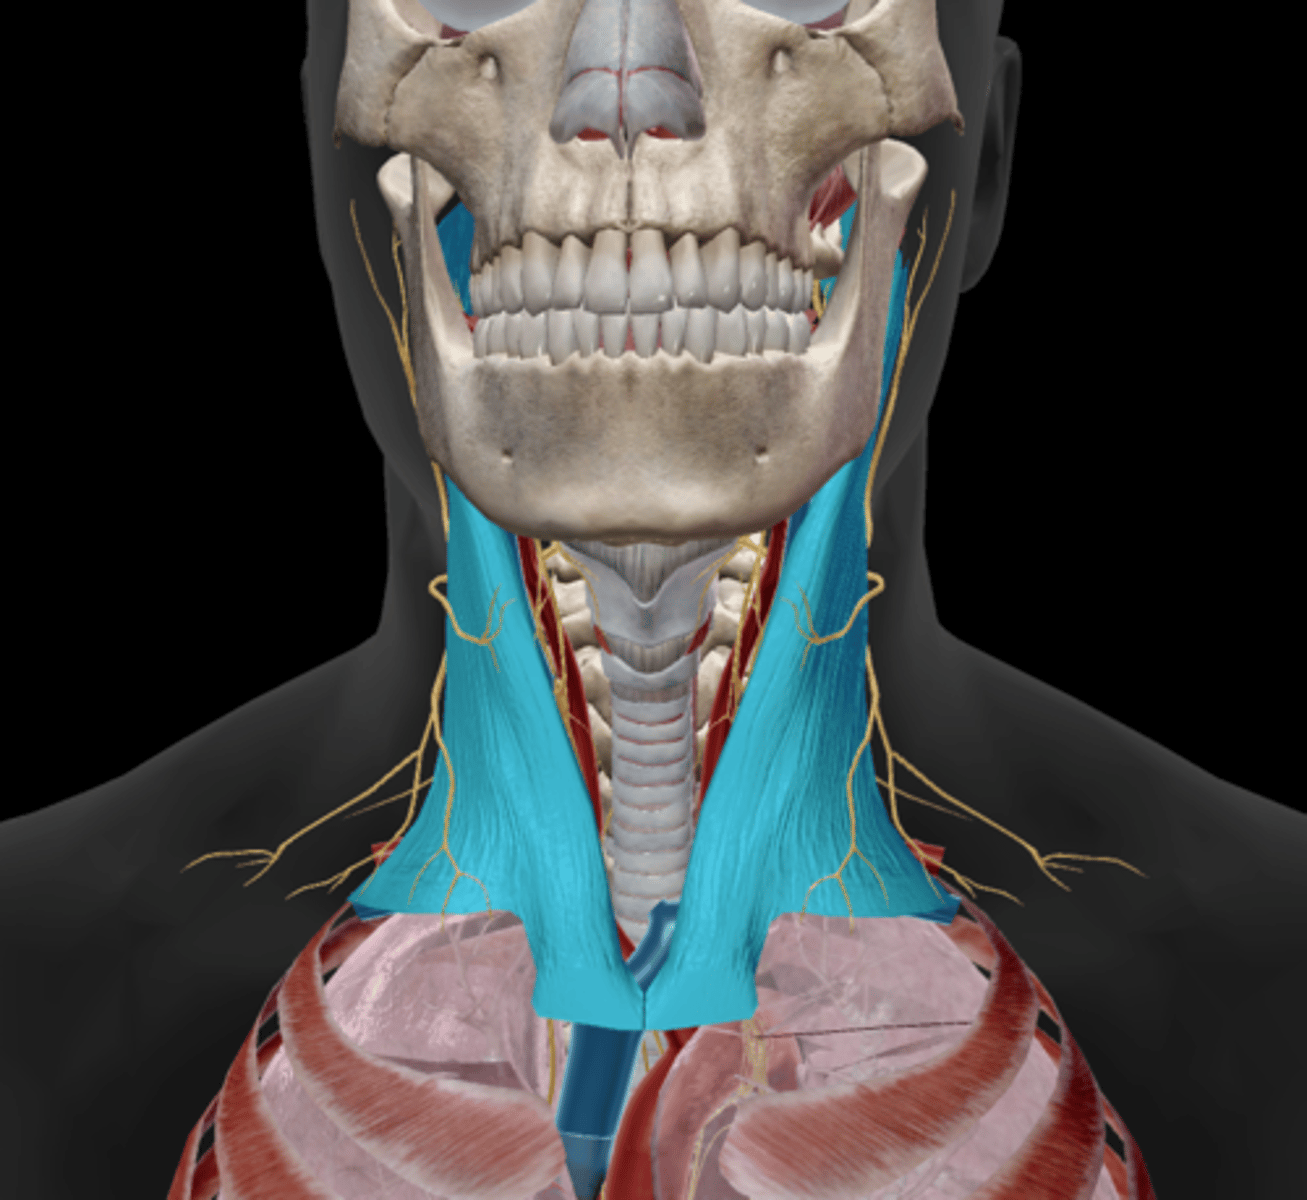

Sternocleidomastoid

Scalenes